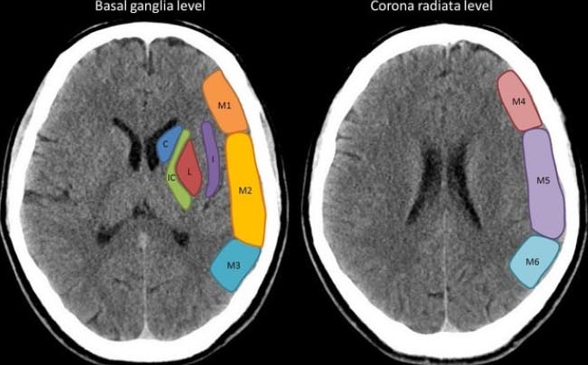

ASPECTS (Alberta stroke program early CT score) — шкала для стандартизации выявления и описания распространения гиподенсивных участков ишемического повреждения головного мозга в бассейне средней мозговой артерии (СМА) на компьютерных томограммах.

Территория кровоснабжения СМА на двух аксиальных срезах (один на уровне таламуса и базальных ядер, другой – сразу над базальными ядрами) делится на 10 участков:

С – хвостатое ядро;

L – чечевицеобразное ядро;

IC – внутренняя капсула;

I – островковая долька;

М1 – передняя кора СМА или оперкулярная зона;

М2 – средняя кора СМА или передне-височная зона;

М3 – задняя кора СМА;

М4 – передняя верхняя территория СМА;

М5 – средняя верхняя территория СМА;

М6 – задняя верхняя территория СМА.

Участки М1-М3 находятся на уровне базальных ганглиев, участки М4-М6 – на уровне желудочков непосредственно над базальными ганглиями...